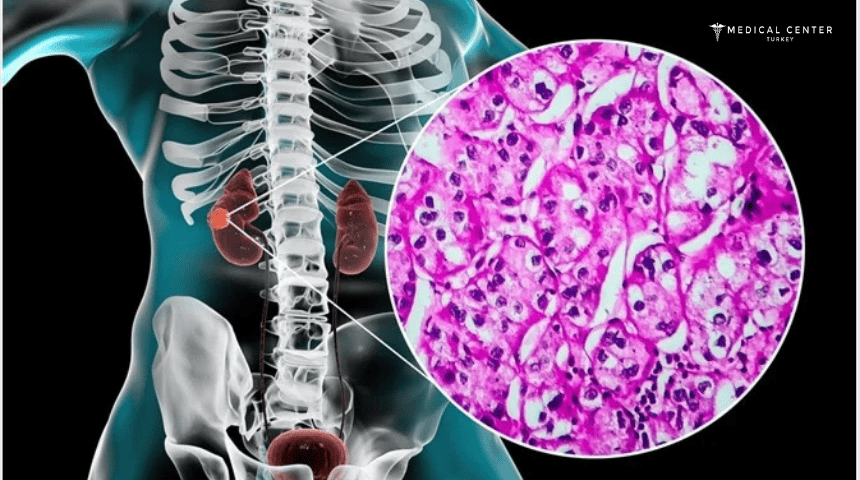

The abnormal proliferation of cells in your kidney tissue is known as kidney cancer. A tumor is a mass that develops from these cells over time. When a change in the cells occurs and they start to divide uncontrollably, cancer starts. A malignant tumor has the potential to spread to other tissues and important organs. This process is known as metastasis.

- Renal cell carcinoma (RCC): Making up over 85% of all kidney cancer cases, RCC is the most prevalent kind in adults. Though it can affect both kidneys, renal cell carcinoma often begins as a solitary tumor in one of them. The kidney’s tubules, which are microscopic tubes that replenish your blood with nutrients and hydration, are where the cancer starts. Clear cell renal cell carcinoma is the most prevalent kind of RCC (ccRCC).